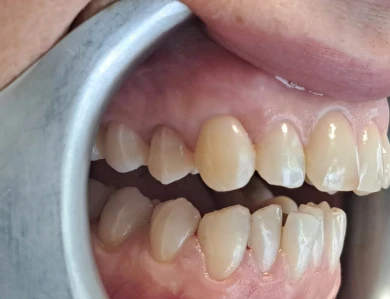

Improving Aesthetics After Orthodontic Treatment

Our patient had multiple discolored teeth and composite fillings placed many years ago. After successful […]